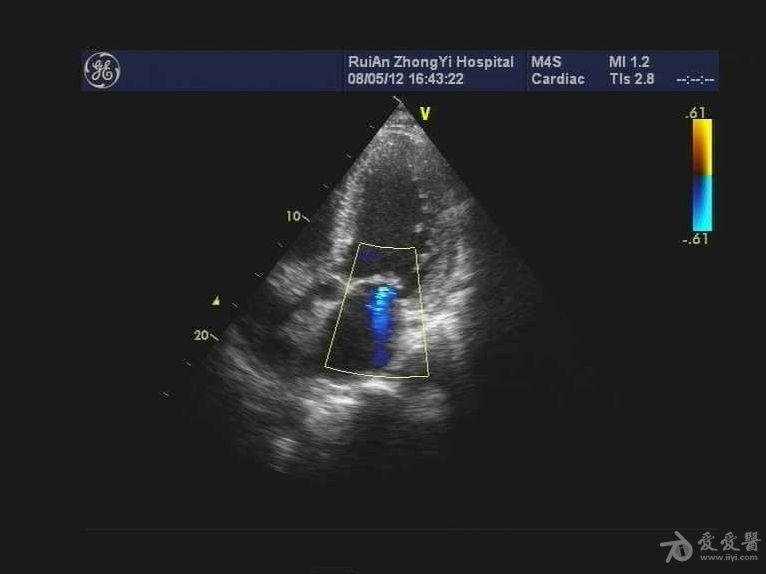

求助心尖部血栓吗?